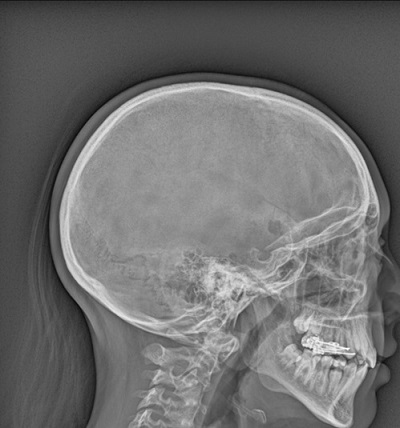

El primer caso es una niña de 11 años que acude a la consulta por tumoración a nivel del cuero cabelludo de tres semanas de evolución. Refiere dolor a la palpación. No refiere traumatismo previo. En la exploración se palpa bulto de consistencia dura, de unos 4×4 cm a nivel frontoparietal, sin signos de flogosis. Se realiza una radiografía craneal en la que se objetiva una imagen radiolucente en parietal derecho, en relación con lesión lítica de 11 mm, sugestiva de HCL ósea monostótica (Fig. 1). Tras este primer diagnóstico de presunción se realiza estudio de extensión (ecografía abdominal, radiografía de tórax, resonancia magnética nuclear cerebral, PET-TAC) con el siguiente resultado: lesión ósea parietal derecha que rompe la tabla interna con extensión epidural y afectación meníngea subyacente. El estudio de extensión fue negativo. Se le practicó una resección quirúrgica sin incidencias, siendo el estudio anatomopatológico compatible con el diagnóstico de presunción: HCL ósea. Tras el resultado del estudio de extensión el diagnóstico definitivo fue HCL ósea monostótica. La evolución posterior ha sido satisfactoria.

| Figura 1. Radiografía craneal en la que se objetiva una imagen radiolucente en parietal derecho, en relación con lesión lítica de 11 mm, sugestiva de HCL ósea monostótica |